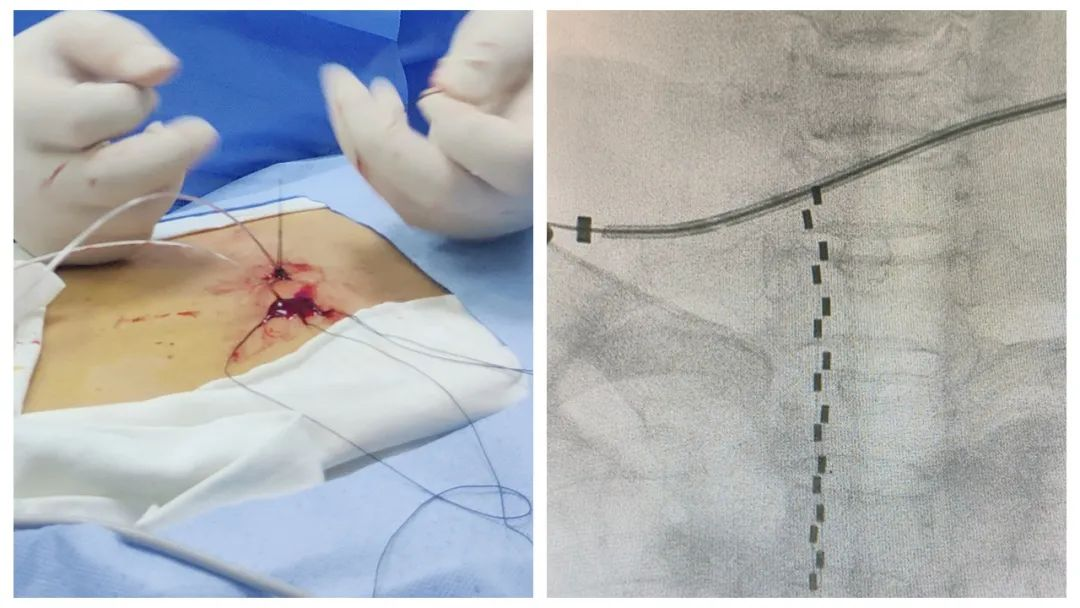

手术当天,麻醉疼痛科团队在影像引导下,准确找到病变的脊髓神经根节段,并将电极放于椎管内,利用电极释放的微弱电流刺激神经改善疼痛症状,成功帮助奶奶彻底摆脱了折磨人的带状疱疹性神经痛。创口仅有“针尖”大小,术后NRS评1-2分,无任何不良反应,镇痛效果满意。

患者的手术创口及精准放置的电极